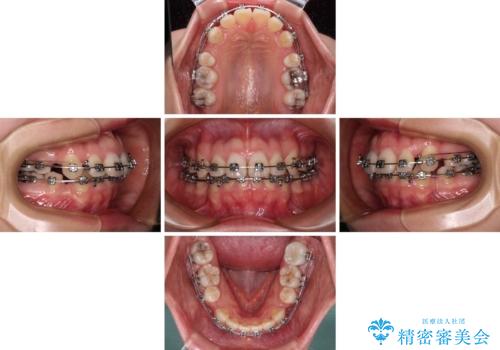

- メタルブラケット

- 2年4ヶ月

口元を積極的に引っ込めるために、上下左右の第一小臼歯を4本抜歯することとし、ワイヤー装置による矯正治療を行うこととしました。

上下前歯がくちばしのように突出していましたが、抜歯矯正により口元が引っ込み、唇が閉じやすくなり、鼻の下の膨れた感じも解消されました。